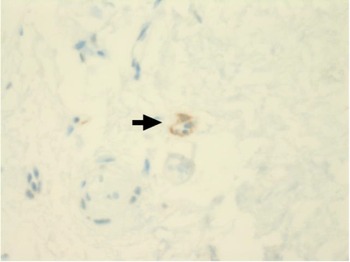

Immunohistochemical staining for pan-cytokeratin AE1/AE3 antibodies demonstrated only very focal residual attenuated surface epithelium (Figure 4). There was strong nuclear and cytoplasmic positivity for S100 immunostain in scattered cells within structures, compatible with Bowman's glands (Figure 5); the same immunostain highlighted small nerve bundles, possibly of trigeminal origin. Immunostaining for angiotensin-converting enzyme 2 (ACE2) receptor showed focal membrane staining in the S100 positive cells in Bowman's glands (Figure 6). There was focal positive staining for synaptophysin, and neurofilament immunostain highlighted small neurites and nerve bundles in lamina propria (Figure 7). No abnormal neural proliferation was identified.

Fig. 5. Immunostain shows strong nuclear and cytoplasmic positivity in scattered cells in structures compatible with Bowman's glands (arrow). The same immunostain highlighted small nerve bundles, possibly of trigeminal origin, not illustrated in this field. (S100 immunostain; ×200)

Fig. 6. Immunostaining for angiotensin-converting enzyme 2 (ACE2) receptor showed focal membrane staining in cells that were also positive for S100 in Bowman's glands (arrow). (ACE2 immunostain; ×200)